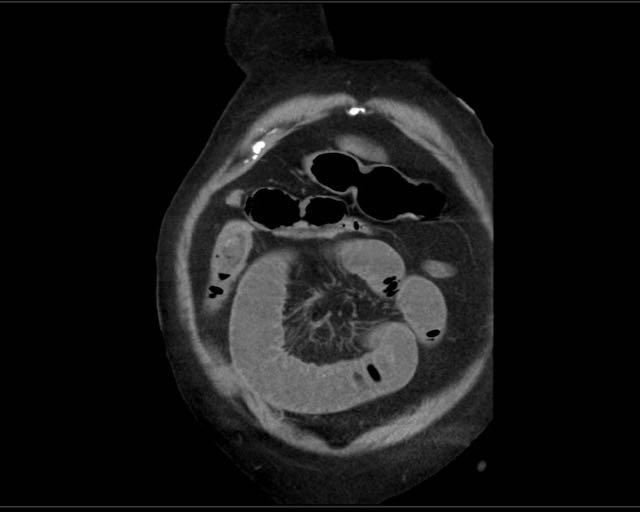

CT trong viêm túi mật cấp

CT có thể rất hữu ích trong các trường hợp siêu âm không cho kết quả chẩn đoán.

Đây là hình ảnh của một bệnh nhân béo phì với đau hạ sườn phải cấp tính trong 6 giờ. CRP 2.

Siêu âm cho thấy túi mật lớn có bùn mật, không quan sát thấy sỏi.

Việc ấn vào túi mật không đáng tin cậy do vị trí cao dưới cung sườn phải.

Không có bất thường siêu âm nào khác.

CT thực hiện cùng ngày cho thấy túi mật lớn với chỉ những thay đổi quanh túi mật kín đáo và không có nguyên nhân nào khác giải thích cho các triệu chứng.

Ngày hôm sau CRP là 105 và CT không tiêm thuốc cản quang lặp lại cho thấy quầng mờ xung quanh túi mật.

Phẫu thuật tiếp theo xác nhận viêm túi mật cấp giai đoạn sớm do sỏi nhỏ trong ống túi mật.